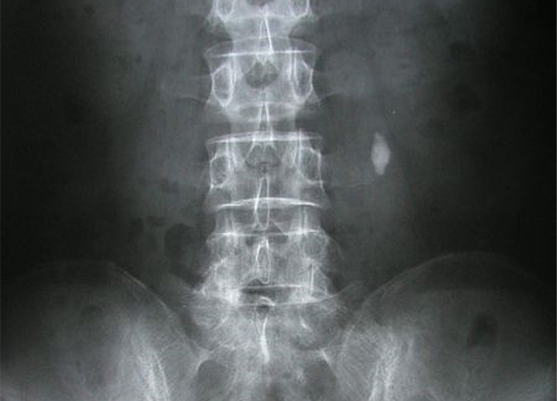

X-ray

대부분 요로결석은 방사선이 투과되지 못하므로

복부 X-ray 촬영을 하게 되면 결석이 하얗게 보입니다.

그러나 15% 정도는 방사선이 투과되는 성분의 결석으로

이런 때에는 KUB(복부 엑스레이 촬영)을 통하여 확인할 수

없어서 경정맥 요로조영술을 해야만 나타납니다.